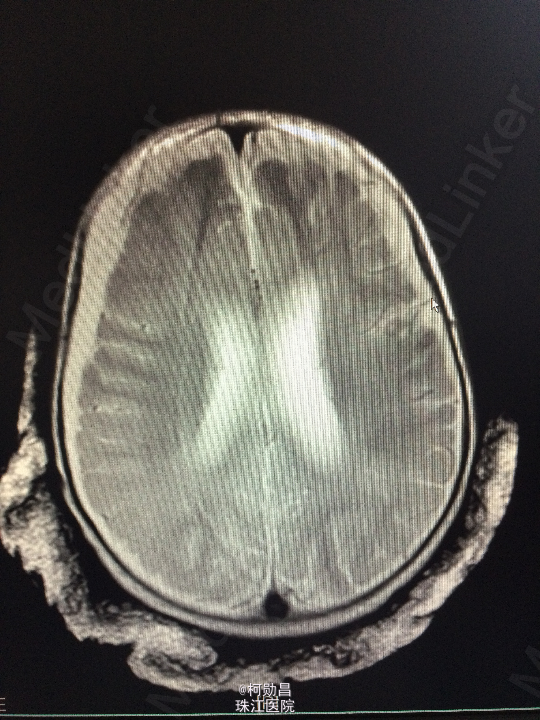

主诉:发热10天,抽搐3天 病史:患儿出生后8个月,因“发热10天,抽搐3天”入院,入院时体温39.3℃,神志不清,反应差。四肢肌张力增高,以双上肢肌力增高明显。病理征未引出。

查体:神志不清,四肢肌力增高 辅助检查:头颅CT提示脑积水并脑脊液外渗,幕上脑室扩张,右侧额颞叶硬膜下脑脊

诊断:化脓性脑膜炎伴脑积水 处理:予内科抗感染治疗,后行脑室腹腔引流术。